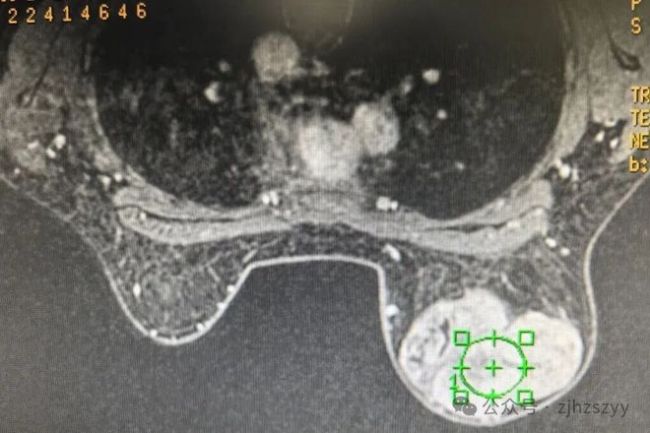

随着时间推移,小刘渐渐发现这个被忽视的硬块在缓慢增大,原本不明显的存在感越来越强。前不久,她终于抽时间来到医院乳腺病科就诊。“就是自己摸到的,一开始没在意,后来慢慢变大了……”入院后检查发现,小刘的右乳肿块已达10cm×12cm,几乎占据整个乳房,外观上右乳已明显大于左侧。医生结合检查情况,建议她尽快手术切除并进行病理检查。

考虑到小刘年轻,对乳房外观有需求,医生在与她充分沟通后,制定了个性化的手术方案:选择在乳房下缘做仅4cm的小切口,既能完整切除肿块,又能最大程度隐藏疤痕,切除后进行美容缝合,再植入假体修复乳房形态。得益于乳腺自然的微下垂状态,术后完全看不出手术痕迹,这让小刘悬着的心放下了大半。

术后病理提示,小刘的肿瘤是良性叶状肿瘤,后续只需遵医嘱定期复查即可。叶状肿瘤是一种生长较快的乳腺肿瘤,因其在显微镜下呈现如树叶脉络般的分叶状结构而得名。尽管绝大多数叶状肿瘤属于良性,并非癌症,但若手术切除不彻底,存在局部复发的可能。因此,一旦发现,应遵循“早发现、早切除”的原则,通过规范手术完整切除,并坚持术后定期复查,这是目前应对该疾病最有效的方法。